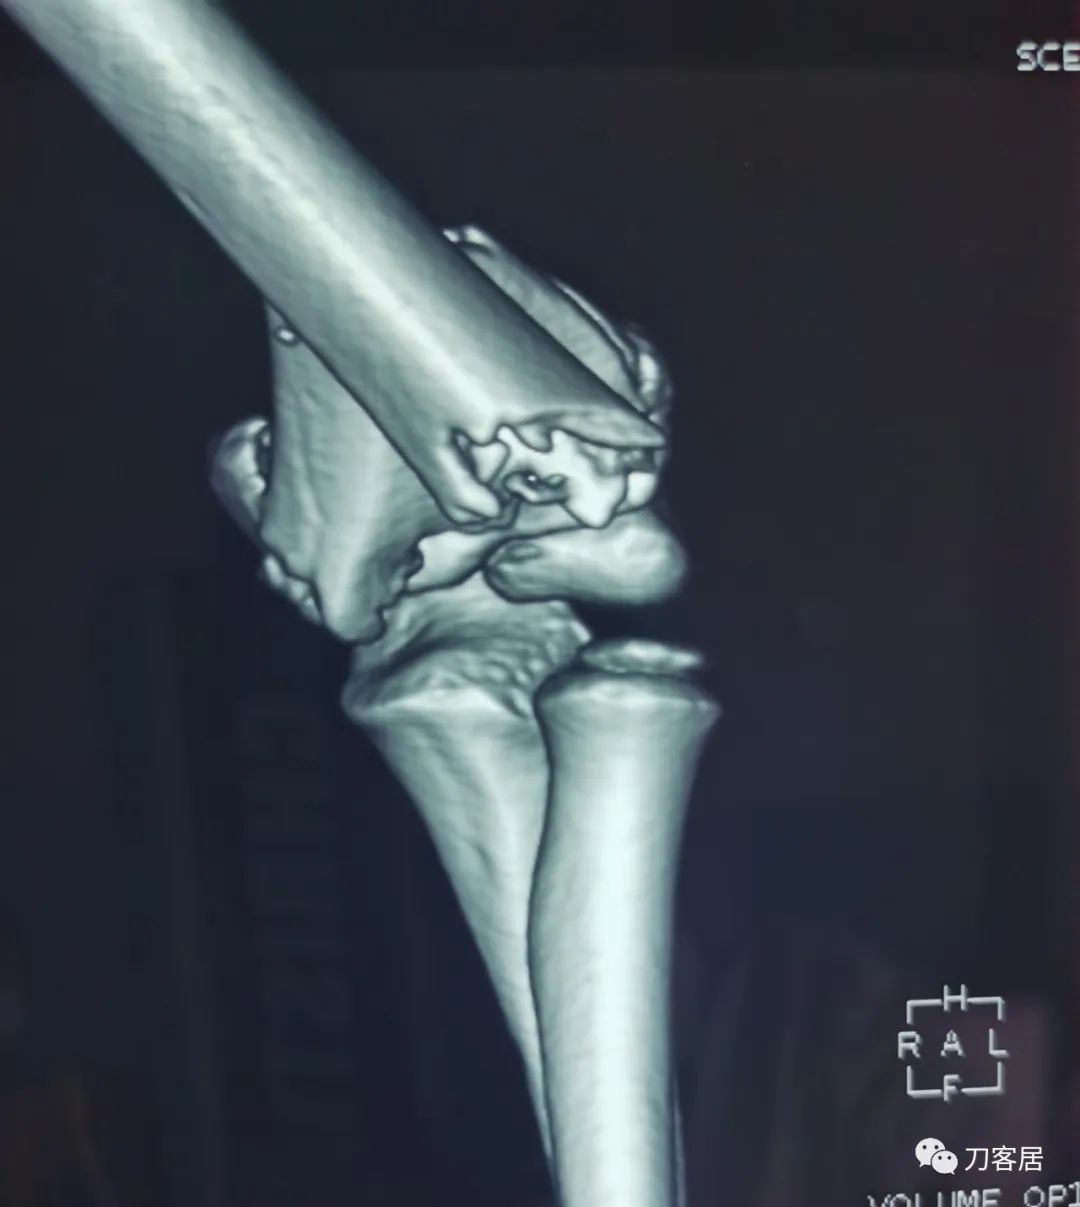

查体:左侧肘关节肿胀明显、疼痛、畸形,局部可见明显青紫瘀斑,左肘关节活动受限,肱骨远端环形压痛(+),局部可及异常活动及骨擦感形成,左上肢末梢桡动脉可触及,左侧腕关节及拇指背伸活动受限,左侧虎口区感觉麻木。辅助检查:自带X线及CT片示:左肱骨髁间粉碎性骨折。

入院诊断:1. 左肱骨髁间粉碎性骨折;2.左肱骨远端骨骺损伤;3. 左桡神经损伤。

20210922当地省中医院三维CT01

20210922当地省中医院三维CT02